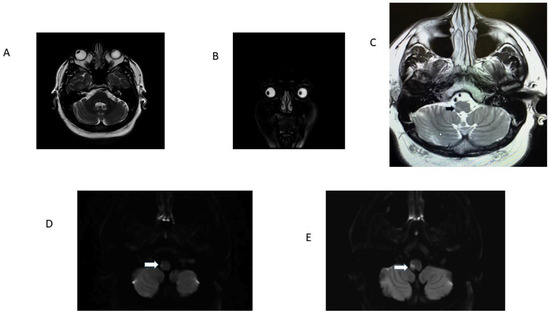

| 1 R OLD 52 | RE: 32.2 LE: 32.2 Hypometric saccades | R lateral medulla, cerebellar tonsil, uvula, and nodulus. | H direction changing | Normal | No | Noted at 32 h exam; present 6 weeks later. Resolved between 6 weeks and 5 months | Ataxia grade 3 to right |

| 2 R OLD 75 | RE: 21.9; LE 22.4. Hypometric saccades | R lateral medulla and lateral cerebellum. | H second degree to L | Normal | Ocular tilt reaction | Noted at 30 h exam; present during hospital stay for 3 days. | Ataxia grade 3 to right |

| 4. L OLD 61 | RE: 25.9; LE:30.3 Hypometric saccades | L lateral medulla. | H second-degree R | Normal | Yes | Noted at 72 h exam. | Ataxia grade 3 to left |

| 5. R OLD 41 | RE: 34.9; LE 25 Hypometric saccades | False-negative in initial MRI. Second MRI: stroke R lateral medulla. | Primary gaze h LBN. Did not follow Alexander’s Law | Normal | Yes | Noted at first exam and at 12 h. Resolved in 48 h. | Ataxia grade 3 to right |

| 6. L OLD 49 F | RE: 21.4; LE: 36.2 Hypometric saccades | False-negative in initial MRI. Second MRI: L lateral medulla. | H 1st-degree RBN | Normal | Yes | Not checked at first visit; present at 36 h exam; lost to f/u. | Ataxia grade 2 to left |

| 7. R OLD 62 F | RE: 13.6; L:0.1 Hypometric Saccade | False-negative in initial MRI. Second MRI: stroke R lateral medulla. | H LBN second degree | Normal | yes | OL Noted at 24 h exam, resolved in 12 h. | Ataxia grade 3 to right |

| 8 R OLD 63 M | RE: 29.3; LE: 27.35 | R lateral medulla. | Second-degree torsional to L shoulder/h-RBN | Normal | OTR | Noted at 32 h exam. | Ataxia grade 3 to right |

| 9 R OLD 51 M | RE: 35.6; LE 26.6 | False-negative in initial MRI. Second MRI: stroke R lateral medulla. | UBN | Normal | yes | Noted at 48 h exam. | Ataxia grade 3 to right |

| 10 R OLD 59 M | RE: 45.3, LE: 42.3 | R dorsolateral medulla. | Bilateral h gaze-evoked nystagmus | Normal | Yes | OLD at 6 h | Ataxia grade 2 to right |

| 11 R OLD 28 M | RE: 35.6, LE: 20.9 | R lateral medulla and cerebellum. | H LBN torsional top pole to left shoulder. | Normal | No | OLD at 24 h. | Ataxia grade 3 to right |

| 12 L OLD 39 M | RE: 22.4, L: 18/1 | L lateral medulla and cerebellum. | H RBN in center fixation, h-gaze-evoked nystagmus. | Normal | No | OLD at 24 h. | Ataxia grade 3 to left |

| 13. R OLD 45 M | RE:40, LE: 34.4 | R lateral medulla. | No nystagmus. | Normal | No | OLD at 6 h. | Ataxia grade 3 to right |